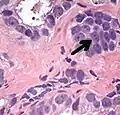

Acinar adenocarcinoma with multiple nucleoli.

Acinar adenocarcinoma with double and eccentric nucleoli.

- Multiple nucleoli

- Eccentric nucleoli[4]